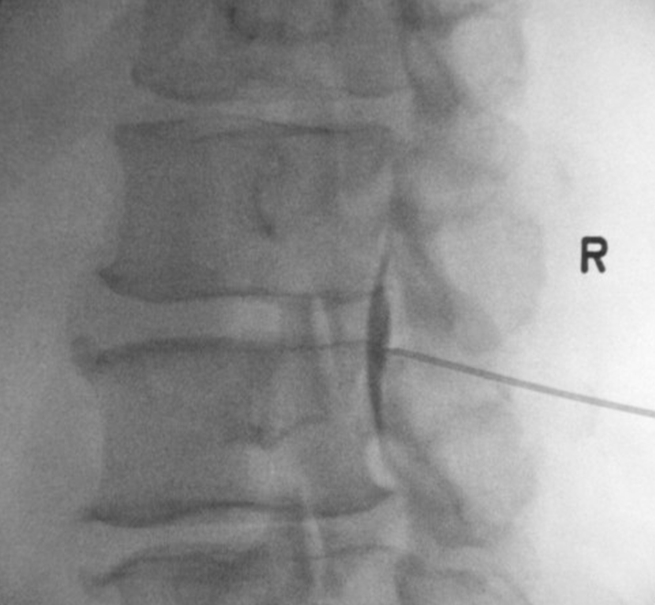

Fig. 3.

Fluoroscopy-guided lumbar epidural steroid injection contralateral oblique view demonstrating caudal spread of contrast within the epidural space.

The patient was evaluated by a neurosurgeon and an interventional pain medicine physician. Physical exam revealed 5/5 strength on manual muscle testing of the bilateral lower extremities, except for 4/5 strength in the right quadriceps and hamstrings muscles. Sensation was intact to light touch in all dermatomes throughout the bilateral lower extremities. Perineal sensation was intact. Right-sided straight-leg raise was positive eliciting increased low back pain with aggravation of pain and tingling down the right leg, including the gluteal region and anterior thigh. Right lower extremity deep tendon reflexes (DTRs) were hypoactive compared to the contralateral side. Babinski's sign was negative. MRI of the lumbar spine revealed high-grade central canal stenosis due to intradural disc herniation completely effacing the subarachnoid space and causing bilateral nerve root compression at the L3-4 level (Figs. 1, 2). The case was discussed among the neurosurgeon, pain physician and patient/family, and the decision was made to pursue a LESI as the patient declined surgery at this time, since he was leaving the city for an out-of-state job. The first LESI was performed roughly 6-weeks post injury. Due to nerve root redundancy above the level of the herniation (L3-4) and intolerance to injection at the L3-4 level due to pain, the epidural space at the L2-3 level was targeted via interlaminar approach under fluoroscopic guidance with notable cranial and caudal contrast spread (Fig. 3). A standardized solution of 1% lidocaine anesthetic and 80 mg of methylprednisolone acetate was injected. There were no procedural complications. At one-week follow-up post injection, the patient reported minimal pain relief, and the decision was made to proceed with a second LESI. Two weeks later, the patient underwent the second LESI by right-sided interlaminar approach at the same L2-3 level without complication. He reported approximately 40% overall improvement with reduction in pain, improved mobility, and increased ability to participate in daily activities and work duties. However, there was no recovery in motor weakness or DTRs at either post-injection follow-up visit.